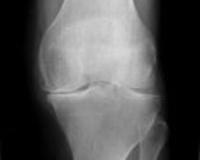

細胞、骨質細胞、髓質細胞(血管和神經)發生了壞死,致骨組織營養中斷或嚴重不足,使骨的代謝障礙,局部骨組織失去了營養,即為骨壞死。骨壞死原則上分為兩大類:一類是由於細菌感染所致的骨壞死,如:骨髓炎、骨結核、化膿性關節炎等。另一類是因缺血造成的骨壞死,如外傷、飲酒、激素藥、寒濕、肝腎虧虛、骨質疏鬆、扁平髖、脊髓異常空洞症等導致的骨壞死。人體任何部位都可能發生骨壞死,臨床以手舟骨、足舟骨、距骨、肱骨頭、肋骨、髕骨、鎖骨、股骨頭為多見,尤以股骨頭髮生率最高。骨壞死發生在股骨頭部位,就叫股骨頭壞死。

是診斷該病最簡單、最實用的方法,但敏感性差,早期單憑X線片不易診斷。骨壞死早期表現為骨質正常或輕度疏鬆,也可出現病變區骨密度相對均勻增高現象,隨後可見負重區有楔狀硬化帶或骨組織囊性病灶形成,進一步出現與關節面平行的“新月狀透亮帶”,關節間隙增寬。最後出現軟骨下骨板及關節面塌陷,骨輪廓改變,階梯狀不連續,骨壓縮加重,同時髖臼關節面也受損,關節間隙狹窄、骨贅形成,整個關節呈現退行性關節炎改變。